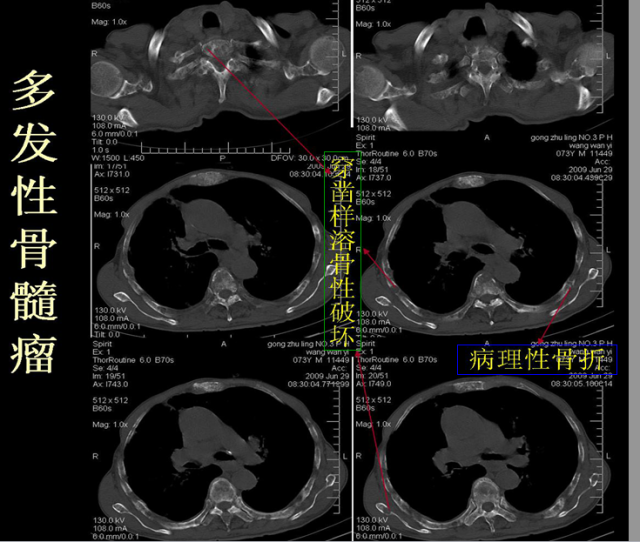

骨折篇

定义:骨折{Fracture}是指骨的完整性和连续性的折裂或粉碎。包括创伤性骨折、疲劳性骨折和病例理性骨折。 临床上以创伤性骨折*常见。